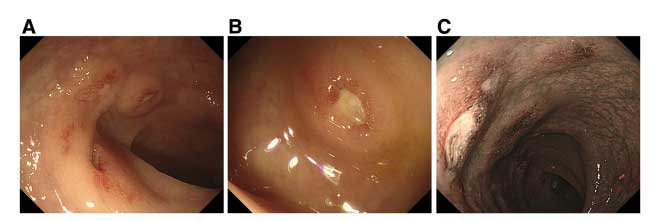

QUIZ: Um caso raro de úlcera intestinal